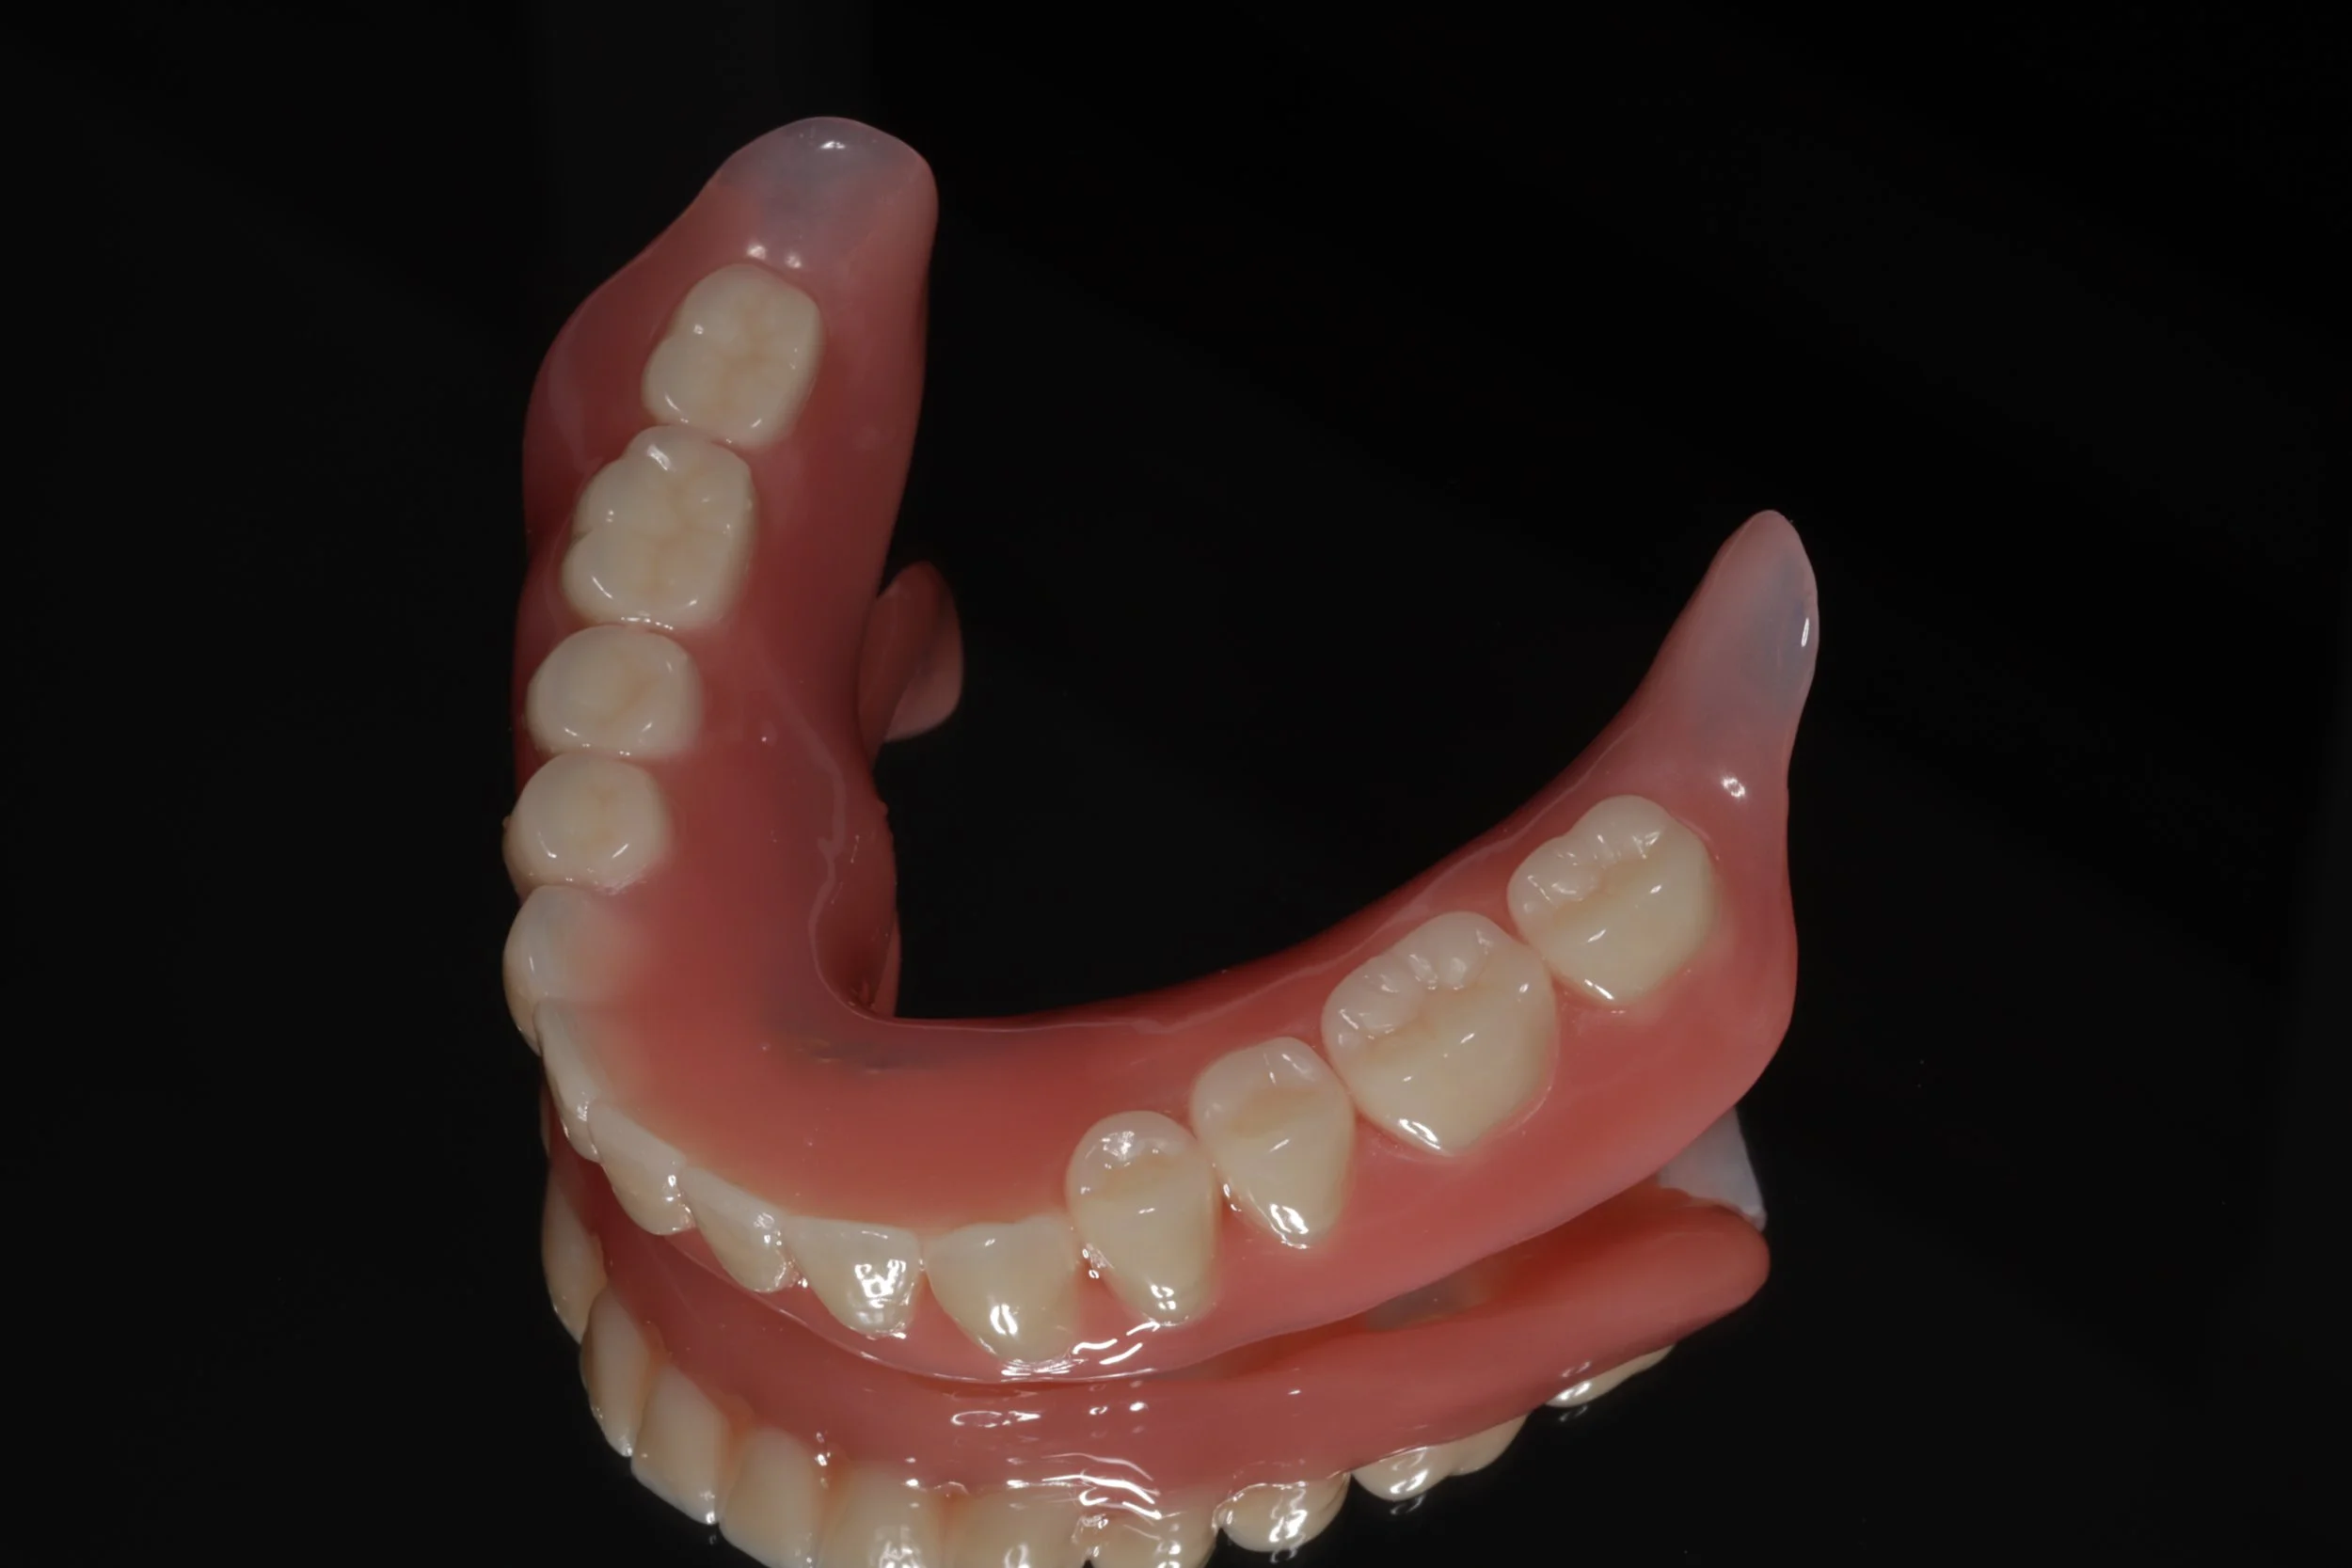

デジタルデンチャー

内側を金属で薄く作る事で違和感の軽減を図りました。前歯の見える部分は、透明の素材を使用。口の状態によってピンク色のときもあります。